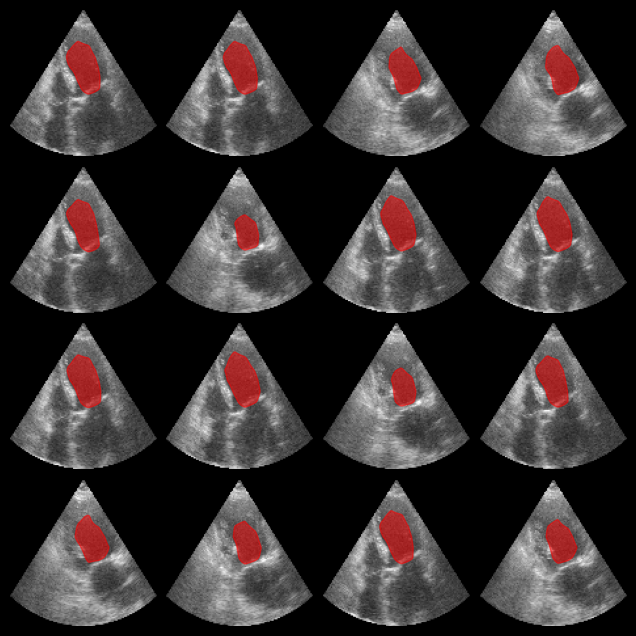

Left ventricle segmentation¶

Here we use the EchoNetDynamic model within the zea framework to segment left ventricle in echocardiograms. Note that in this notebook, we use the original model, but perform inference on the CAMUS dataset, which is a different dataset than the one used to train the model.

Now let’s load some data (for more info see the zea_data_example notebook), and perform inference on the data to segment the left ventricle. Note that the performance of the model is not as good on the CAMUS dataset as it is on the original EchoNetDynamic dataset, but it still provides a good example of how to use the model within the zea framework.

fig, _ = plot_image_grid(batch, vmin=0, vmax=1)

axes = fig.axes[:n_imgs]

for ax, mask in zip(axes, masks):

add_shape_from_mask(ax, mask, color="red", alpha=0.5)

plt.show()